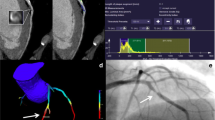

Fractional flow reserve derived from coronary CT (FFR-CT) is a noninvasive physiological technique that has shown a good correlation with invasive FFR. However, the use of FFR-CT is restricted by strict application standards, and the diagnostic accuracy of FFR-CT analysis may potentially be decreased by severely calcified coronary arteries because of blooming and beam hardening artifacts. The aim of this study was to evaluate the utility of deep learning (DL)-based coronary computed tomography (CT) data analysis in predicting invasive fractional flow reserve (FFR), especially in cases with severely calcified coronary arteries. We analyzed 184 consecutive cases (241 coronary arteries) which underwent coronary CT and invasive coronary angiography, including invasive FFR, within a three-month period. Mean coronary artery calcium scores were 963 ± 1226. We evaluated and compared the vessel-based diagnostic accuracy of our proposed DL model and a visual assessment to evaluate functionally significant coronary artery stenosis (invasive FFR < 0.80). A deep neural network was trained with consecutive short axial images of coronary arteries on coronary CT. Ninety-one coronary arteries of 89 cases (48%) had FFR-positive functionally significant stenosis. On receiver operating characteristics (ROC) analysis to predict FFR-positive stenosis using the trained DL model, average area under the curve (AUC) of the ROC curve was 0.756, which was superior to the AUC of visual assessment of significant (≥ 70%) coronary artery stenosis on CT (0.574, P = 0.011). The sensitivity, specificity, positive and negative predictive value (PPV and NPV), and accuracy of the DL model and visual assessment for detecting FFR-positive stenosis were 82 and 36%, 68 and 78%, 59 and 48%, 87 and 69%, and 73 and 63%, respectively. Sensitivity and NPV for the prediction of FFR-positive stenosis were significantly higher with our DL model than visual assessment (P = 0.0004, and P = 0.024). DL-based coronary CT data analysis has a higher diagnostic accuracy for functionally significant coronary artery stenosis than visual assessment.